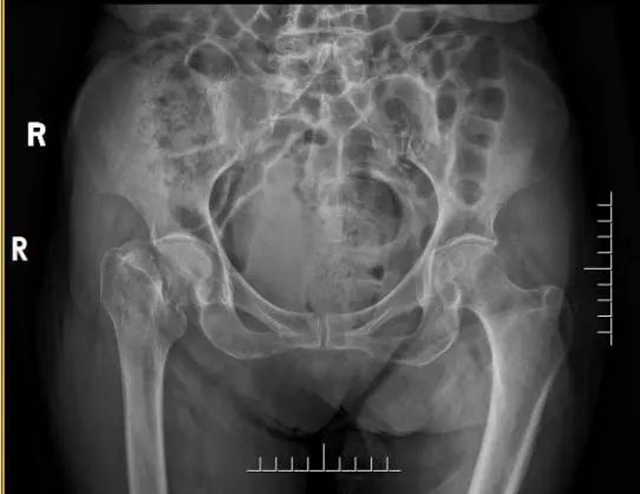

张婆婆术前X线

李忠教授说道:“张婆婆年龄很大,同时右侧股骨颈发生了骨折。老年人发生股骨颈骨折,通常被称为人生最后一次骨折。特别是80岁以上的高龄老人如果发生这种骨折,保守治疗死亡率高达30%以上,手术治疗可将死亡率降低一半以下。所以一般情况下,我们建议发生股骨颈骨折的老人,只要能耐受麻醉,应及时手术,提高其生存率。因此,我们要尽可能快的为张婆婆进行手术,缩短从受伤到手术时间,就是抢救生命!”